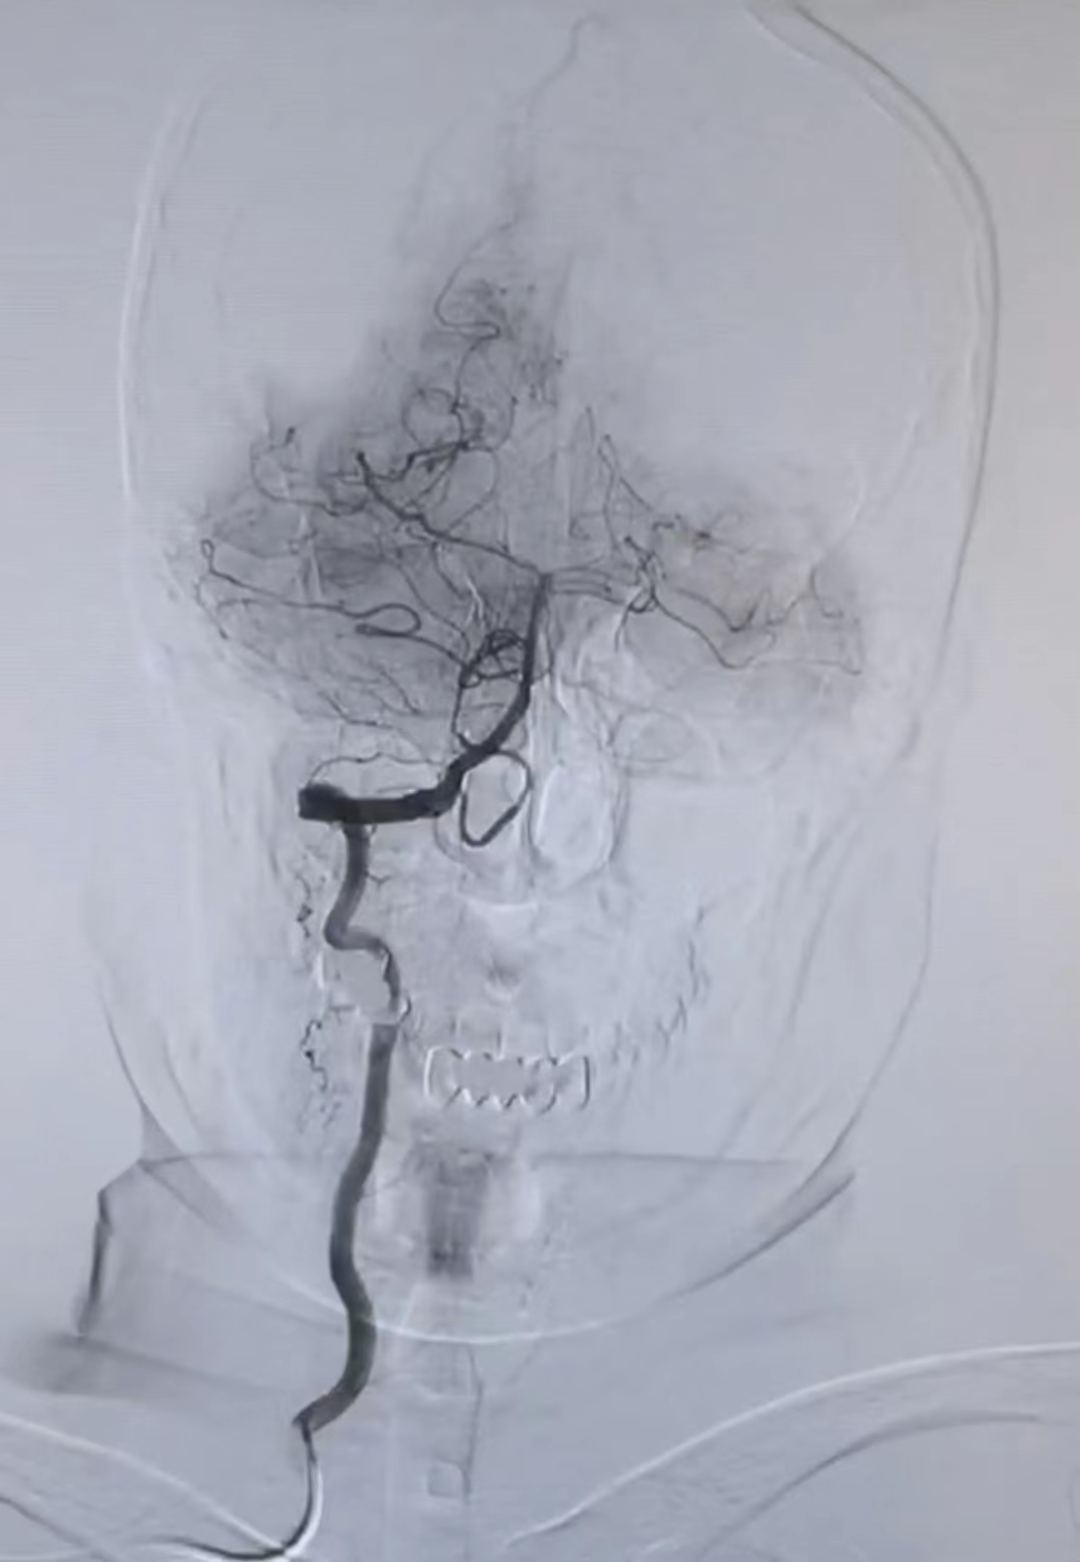

近日,齐医附属一院神经外科二组成功完成医院首例“经桡动脉穿刺行全脑血管造影术”,这标志着我院神经外科脑介入诊疗水平再上一个新台阶。

数字减影全脑血管造影(DSA)是诊断脑血管病的重要检查方法之一,是目前评价脑血管病的“金标准”。做全脑血管DSA检查有两种穿刺插管方式。一种是经股动脉穿刺插管,一种是经桡动脉穿刺插管。常规以往我们都用经股动脉穿刺置管,但一些老年患者或有腰部疾症患者的耐受性较差,很多需要做全脑血管造影术检查的患者一听说要卧床24小时,制动12小时都纷纷打退堂鼓。由此,患者对常规全脑血管造影术的接受程度不高,且穿刺下肢制动后容易形成下肢静脉血栓,造成肺栓塞风险。

而桡动脉位于人体腕部,经桡动脉脑血管造影,只需在手腕部的一根血管中引入造影导管,就可进入颈内动脉、锁骨下动脉、椎动脉,完成脑血管造影检查。经此途径实施造影穿刺部位损伤小,出血少,并发症少,术后即可下床活动,舒适度高。

经桡动脉冠状血管造影在心脏介入领域普遍应用,已成为冠状造影的首选入路途径。由于脑血管解剖复杂,迂曲多,因此经桡动脉全脑血管造影术在手术技术方面难度较大,对医生操作要求很高。本院神经外科二组已成功开展此项技术,为广大脑血管病患者开辟了新的检查治疗途径,体现了快速、精准、微创的救治理念。今后,该类手术将积极推广常规开展。

DSA是一种崭新的X线检查新技术。它是先选一入路动脉,一般选用股动脉(常规),亦可选择桡动脉入路(新技术)。通过股动脉或桡动脉放置一动脉鞘,通过该动脉鞘管选用不同导管,在导丝引导下,选进所要显示动脉,注入含碘造影剂。造影剂所经过的血管轨迹连续摄片,通过电子计算机辅助成像为脑血管数字减影造影(DSA)。DSA可清楚地显示脑动脉管腔狭窄、闭塞、侧支循环建立情况等,对于脑出血、蛛网膜下腔出血,可进一步查明导致出血的病因,如动脉瘤、动静脉畸形、动静脉瘘等。目前被公认为血管性疾病诊断的“金标准”。

和临床常用的MRA、CTA相比,DSA不仅可提供直观的颈部和脑血管实时影像,而且可以充分显示从动脉到静脉整个循环过程的周期、形态、分布与走行等动态变化,使临床医师全面了解和判断疾病的可能原因、发病部位、病变程度,以便选择最佳的治疗方式。